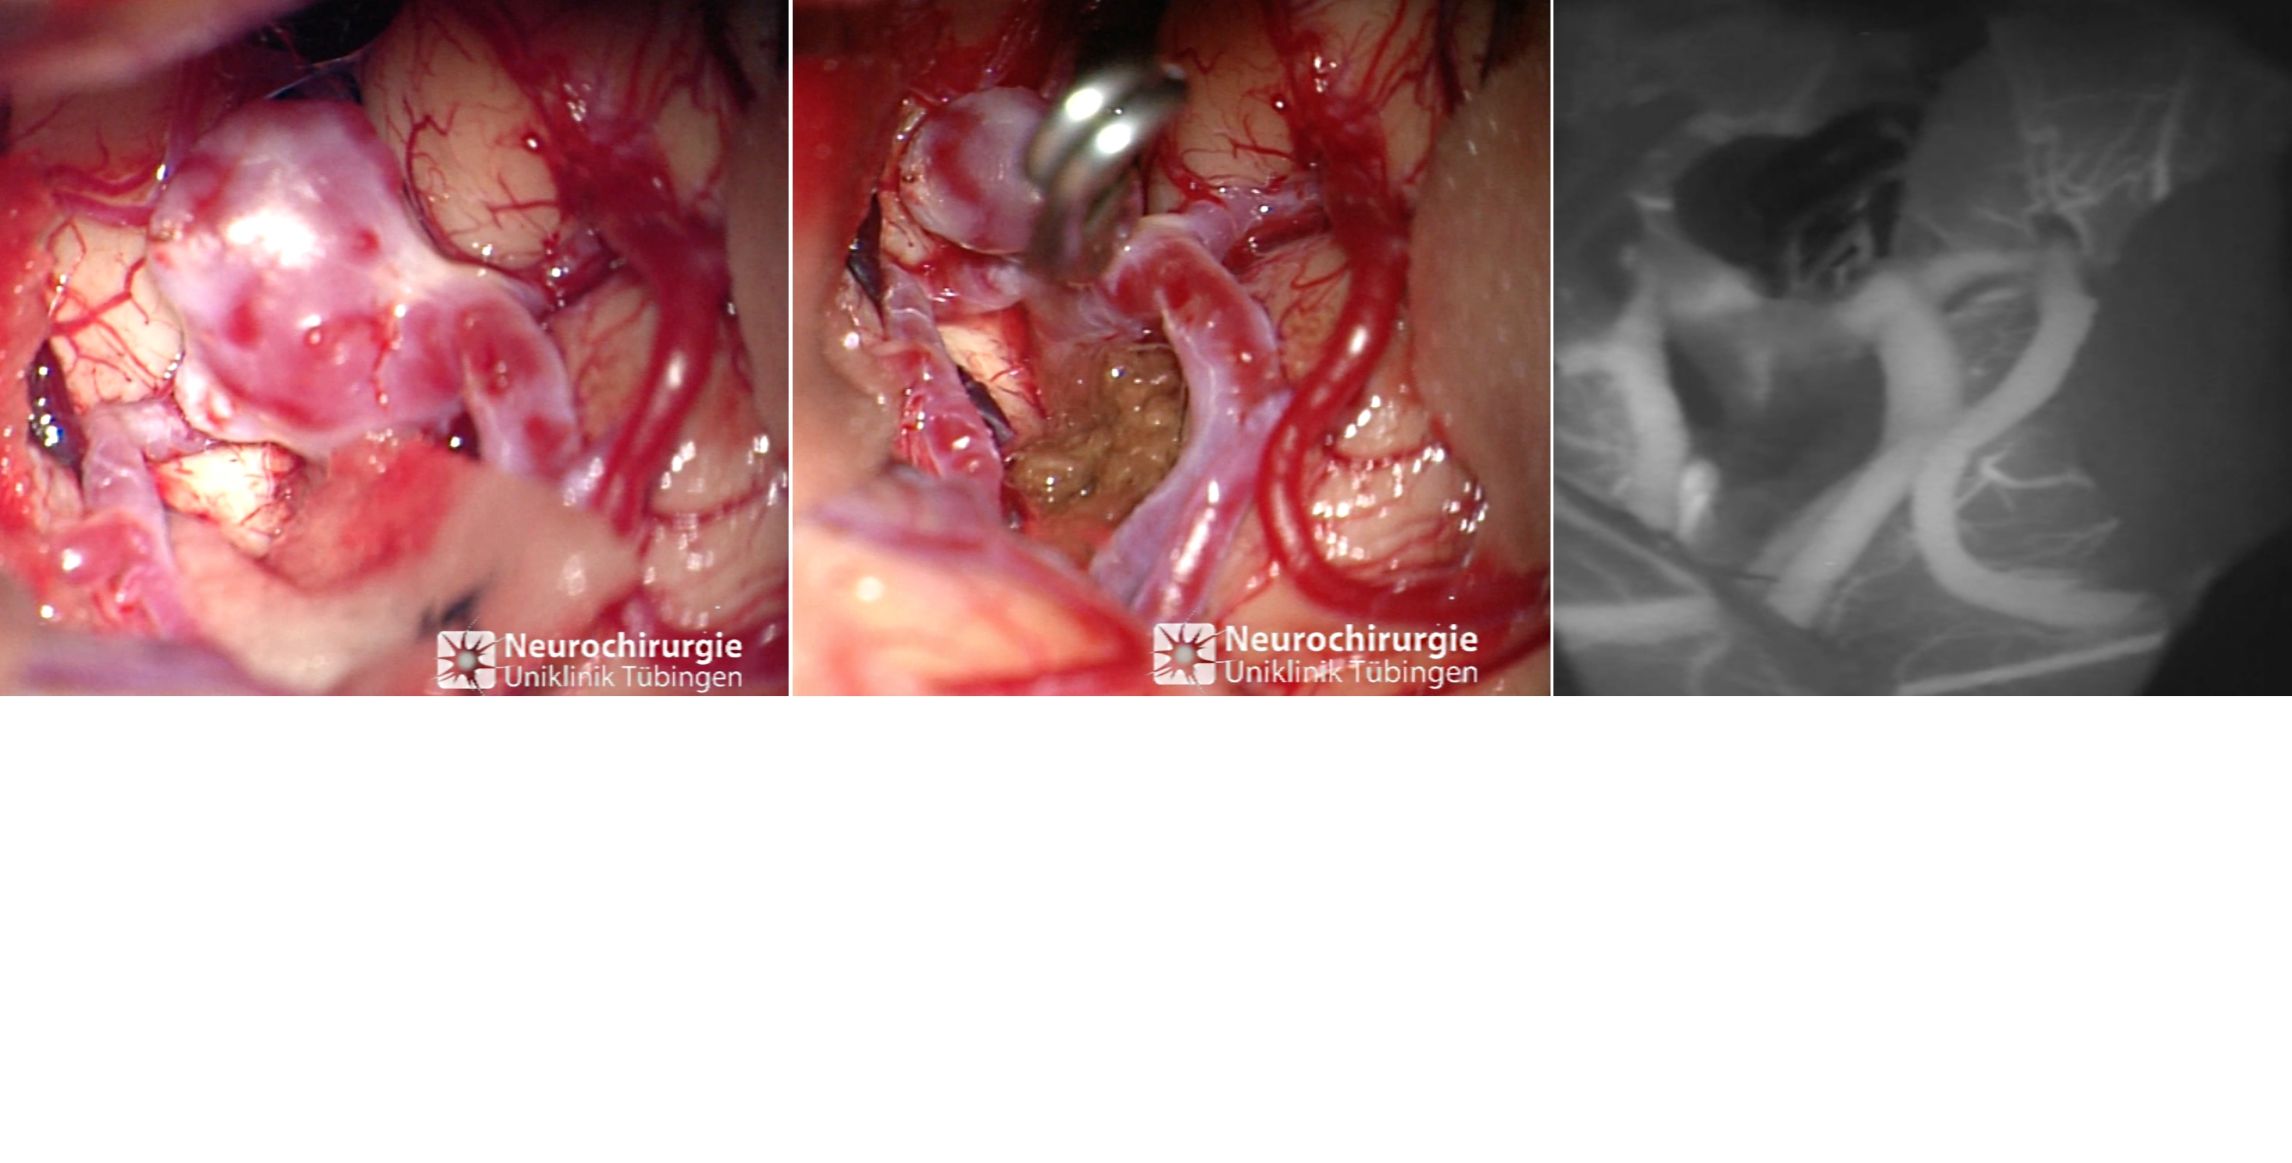

Angiographiesche Darstellung eines Aneurysmas

Angiographiesche Darstellung eines Aneurysmas vor (links) und nach (rechts) dem Coiling